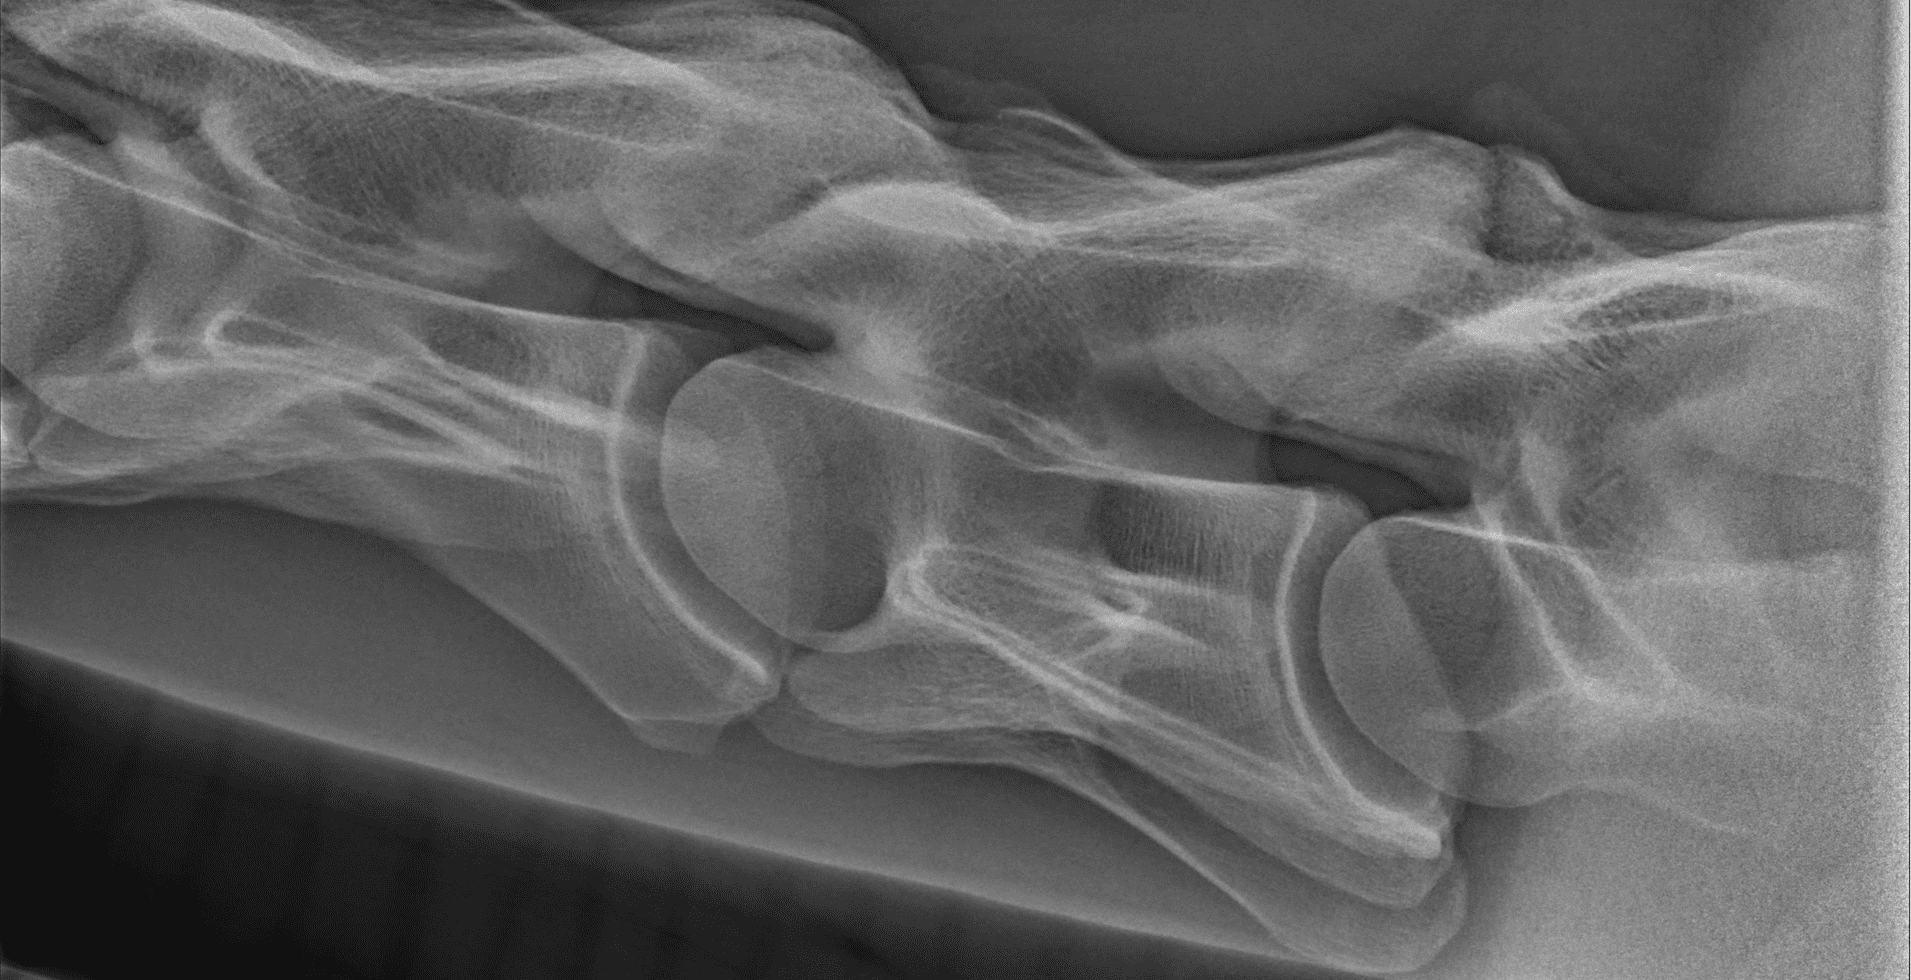

Röntgen

Een röntgenapparaat kan met behulp van röntgenstralen foto’s maken van de binnenkant van het lichaam. Vanwege hun doordringende vermogen kan met name het skelet op die manier goed bekeken worden, maar ook andere organen zoals de longen. Het röntgenonderzoek heeft een vlucht genomen met de introductie van de digitale röntgen. Beelden kunnen worden vergroot, contrasten groter of kleiner gemaakt en informatie kan via de computer makkelijk en snel worden uitgewisseld.

Bij onderzoek naar een stoornis aan het bewegingsapparaat (orthopedisch onderzoek) wordt röntgen intensief gebruikt. Röntgenonderzoek laat veranderingen zien zoals kreupelheid, fracturen, botontstekingen en standsafwijkingen. Ook aanhechtingsproblemen van pezen en banden met botafwijkingen zijn in beeld te brengen. Daarnaast wordt röntgenonderzoek gebruikt bij problemen aan het hoofd en het gebit. Bij onderzoek naar problemen aan de luchtwegen kunnen röntgenfoto’s gebruikt worden voor het stellen van een diagnose. Voor een röntgenonderzoek wordt het paard onder lichte verdoving gebracht, zodat deze keurig stil staat en minder onder de indruk is van alle apparatuur. Om problemen in beeld te brengen zijn vaak meerdere röntgenfoto’s van dezelfde locatie noodzakelijk. Eén foto zegt meestal onvoldoende. Bij de keuring van het paard wordt een min of meer standaard set gemaakt. Ook daarbij worden van diverse gewrichten meerdere röntgenfoto’s uit verschillende richtingen gemaakt.